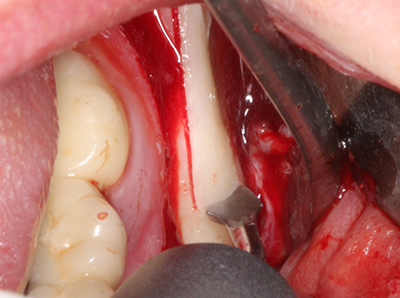

Пиезохирургията има допълнителни предимства при събиране на костни блокове. В допълнение към високата прецизност при остеотомията, описана по-горе, употребата на фините режещи накрайници значително намаляват загубата на материал. Голяма загуба на материал по време на събиране може да се очаква с дебелите накрайници, особено при употреба на борери Линдеман (Lakshmiganthan, Gokulanathan et al. 2012). Базалното разделяне, което е необходимо, особено за присадка на блок при ретромолар, е улеснено от специално създадени правоъгълни триони. В резултат на това, пиезохирургията е разглеждана като прецизна, улеснена и безопасна процедура за събиране на костни блокове в ретромоларното пространство (Happe 2007) (Фиг. 1-12).